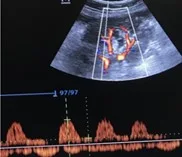

A 53 year old man with heart failure with reduced ejection fraction (~37%) secondary to non-ischemic cardiomyopathy and end-stage kidney disease (ESKD) recently initiated on hemodialysis underwent a right upper quadrant ultrasound for elevated liver function tests. Despite a radiology report indicating “normal liver morphology and hemodynamics,” a review of images by the nephrology team revealed severe venous congestion. This was evidenced by a dilated inferior vena cava (IVC) with an approximate anteroposterior diameter of 3 cm, systolic (S-wave) reversal in the hepatic vein flow, and a pulsatile portal vein with some flow reversal (Figure 1). These sonographic findings are consistent with VExUS grade 3 (Figure 2).

Figure 1. Radiology-performed scan images demonstrating a dilated inferior vena cava (approximately 3 cm), S-wave reversal on hepatic vein Doppler and a pulsatile portal vein (below-the-baseline blebs represent flow reversal).